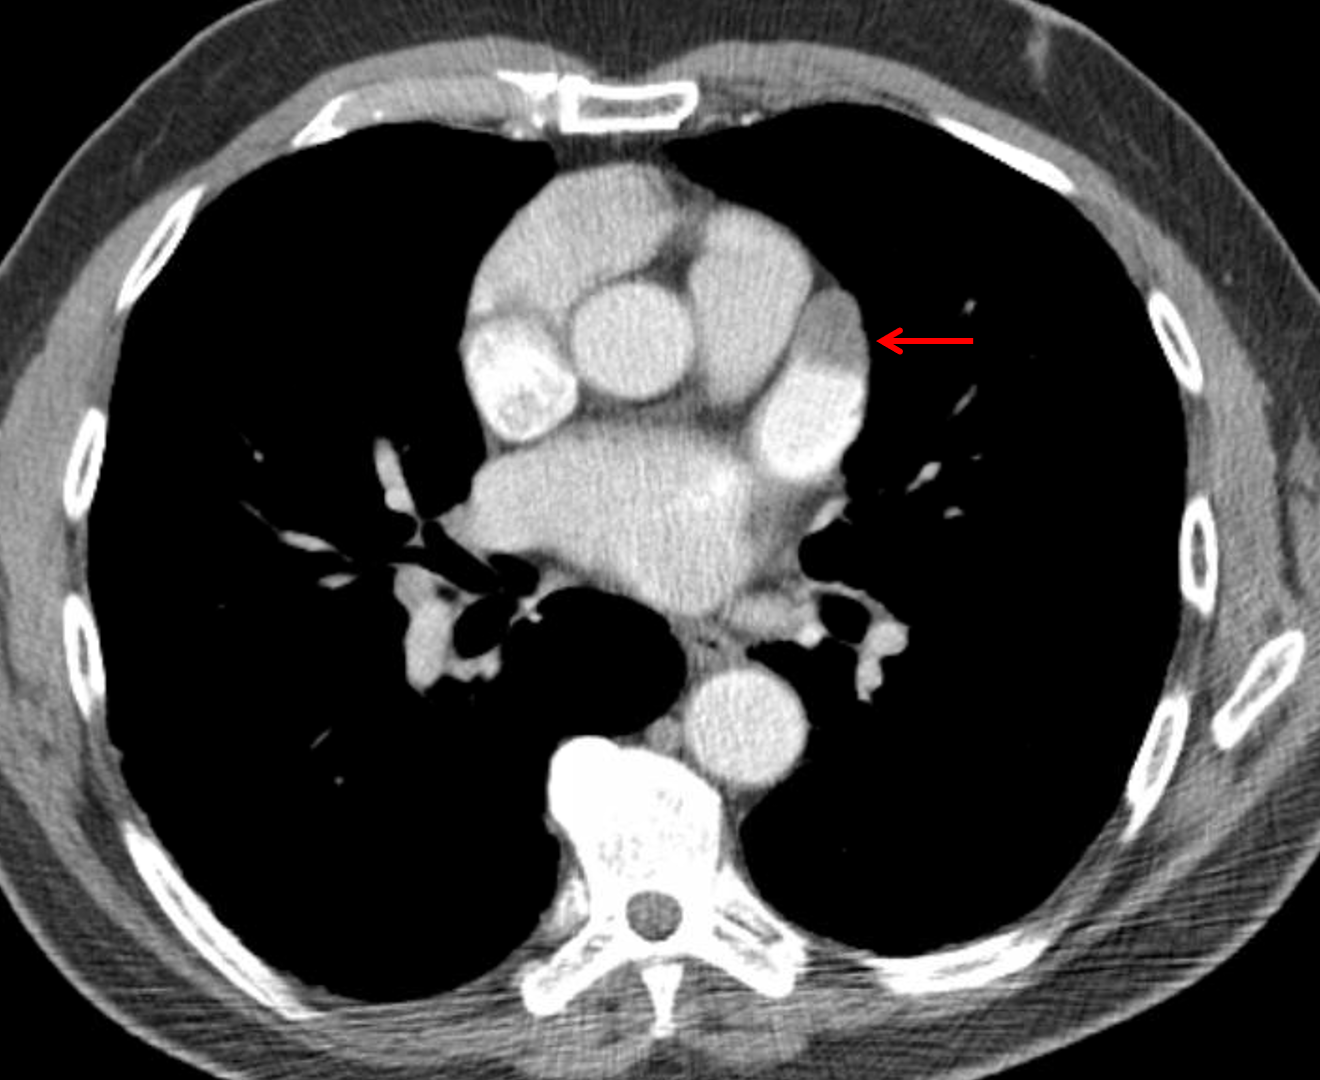

Age: 82

Sex: Male

Indication: Dyspnea, lung cancer undergoing radiation therapy

Sample ReportSpiculated right upper lobe mass consistent with reported history of lung cancer. Surrounding architectural distortion could relate to the neoplasm itself or developing postradiation changes.

Filling defect in the left atrial appendage concerning for thrombus.